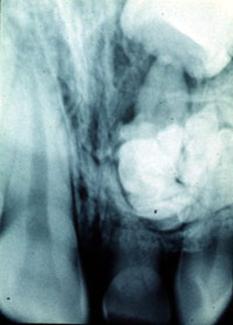

ii. Diferite formatiuni supranumerare ( dinti, odontoame) influenteaza ordinea si traseul.

c. Traumatismele in dentitia temporara : pierdere foarte devreme a dintelui temporar cu formarea unui capac osteo-fibros in locul lui. Capacul va fi foarte greu strapuns de dintele permanent. Ca tratament se va face tunelizarea canalului in acea zona